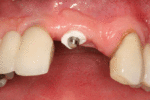

Basic implant surgical procedure

The area of the mouth that is missing a tooth is identified.

An area with a single missing tooth

An incision is made across the area and the flap of gingiva is opened to show the bone of the jaw.

An incision is made across the gingiva, and the flap of tissue is reflected to show the bone of the jaw.

A series of slow-speed drills create and gradually enlarge a site in the jaw for the implant to be placed. The hole is called an osteotomy.

Once the bone is exposed, a series of drills create and gradually enlarge a site (called an osteotomy) for the implant to be placed.

The implant fixture is turned into the osteotomy. Ideally, it is completely covered by bone and has no movement within the bone.

A healing abutment is attached to the implant fixture and the gingiva flap is sutured around the healing abutment.

A healing abutment is attached to the implant fixture, and the flap of gingiva is sutured around the healing abutment.